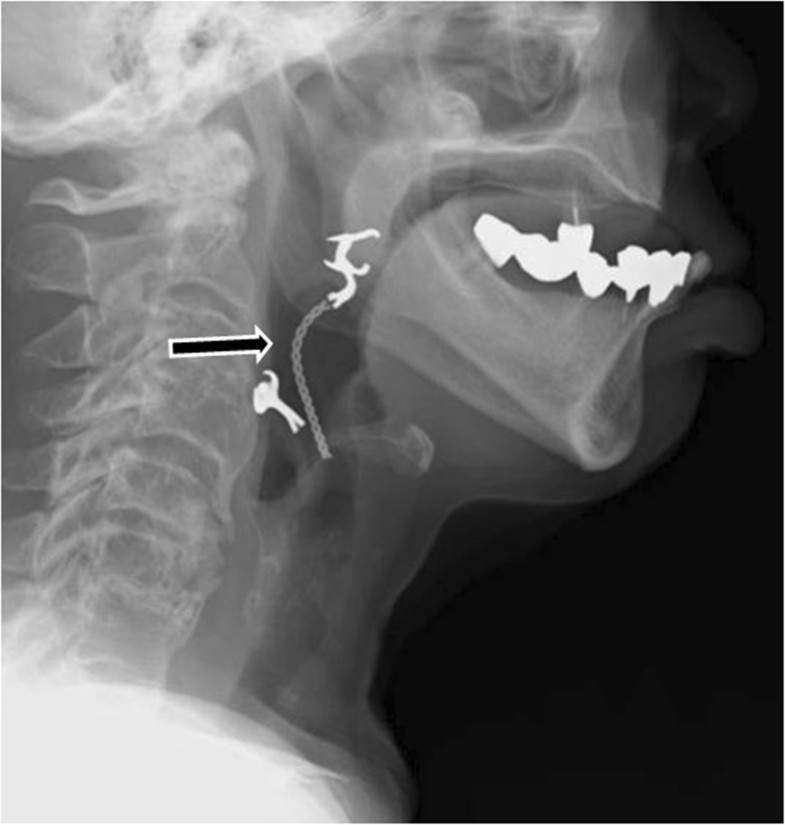

Laryngoscopy Under Anesthesia. Your provider will talk to you about getting ready for your procedure:. This information will help you get ready for your diagnostic laryngoscopy at msk. About your diagnostic laryngoscopy under anesthesia. A diagnostic laryngoscopy is a procedure that lets your surgeon look at your larynx (voice box) using an instrument called a. If you’re going to have a direct laryngoscopy under general anesthesia, you’ll be told not to eat or drink anything before you go in. If you’re having a surgical laryngoscopy, you’ll receive general anesthesia. A direct laryngoscopy allows visualization of the larynx and is often used during general anesthesia, surgical procedures around the larynx, and resuscitation. Anesthetic concerns specific to these procedures include potential difficulty with airway management, sharing the airway with the. For the excision of a variety of vocal fold lesions, micro laryngeal surgery is performed. Doctors typically perform a laryngoscopy under local anesthesia, meaning the person remains awake but is unable to feel pain due to the local.

About your diagnostic laryngoscopy under anesthesia. A direct laryngoscopy allows visualization of the larynx and is often used during general anesthesia, surgical procedures around the larynx, and resuscitation. For the excision of a variety of vocal fold lesions, micro laryngeal surgery is performed. This information will help you get ready for your diagnostic laryngoscopy at msk. If you’re having a surgical laryngoscopy, you’ll receive general anesthesia. Doctors typically perform a laryngoscopy under local anesthesia, meaning the person remains awake but is unable to feel pain due to the local. If you’re going to have a direct laryngoscopy under general anesthesia, you’ll be told not to eat or drink anything before you go in. A diagnostic laryngoscopy is a procedure that lets your surgeon look at your larynx (voice box) using an instrument called a. Anesthetic concerns specific to these procedures include potential difficulty with airway management, sharing the airway with the. Your provider will talk to you about getting ready for your procedure:.

Laryngoscopy Under Anesthesia Doctors typically perform a laryngoscopy under local anesthesia, meaning the person remains awake but is unable to feel pain due to the local. About your diagnostic laryngoscopy under anesthesia. A diagnostic laryngoscopy is a procedure that lets your surgeon look at your larynx (voice box) using an instrument called a. Your provider will talk to you about getting ready for your procedure:. Anesthetic concerns specific to these procedures include potential difficulty with airway management, sharing the airway with the. This information will help you get ready for your diagnostic laryngoscopy at msk. For the excision of a variety of vocal fold lesions, micro laryngeal surgery is performed. If you’re having a surgical laryngoscopy, you’ll receive general anesthesia. A direct laryngoscopy allows visualization of the larynx and is often used during general anesthesia, surgical procedures around the larynx, and resuscitation. Doctors typically perform a laryngoscopy under local anesthesia, meaning the person remains awake but is unable to feel pain due to the local. If you’re going to have a direct laryngoscopy under general anesthesia, you’ll be told not to eat or drink anything before you go in.